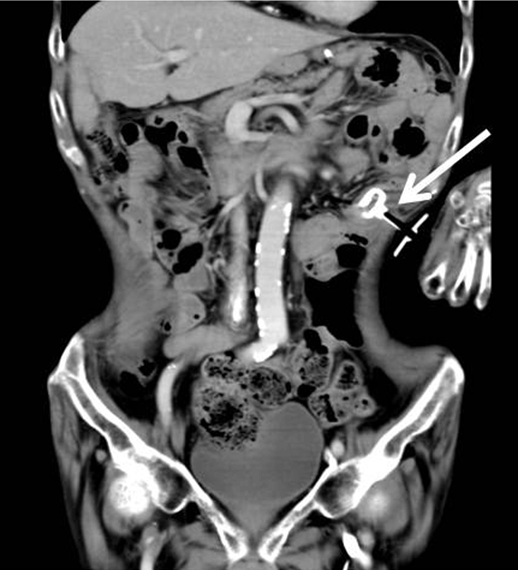

We replaced jejunal tube four times after USPEJ because the tube looked old. At the replacement of jejunal tube we used EndoVive Bumper Gtube (Boston scientific, USA) as new jejunal tube. After we pulled out the first PEG tube, we inserted EndoVive percutaneously. No technical difficulty and complication was encountered. We cannot use balloon type exchange tube because the balloon occludes the jejunum. We took CT to make sure that the tube was in jejunum (Figure 3).

Figure 3: CT scan after replacement of jejuinal tube to EndoVive Bumper G tube (arrow).